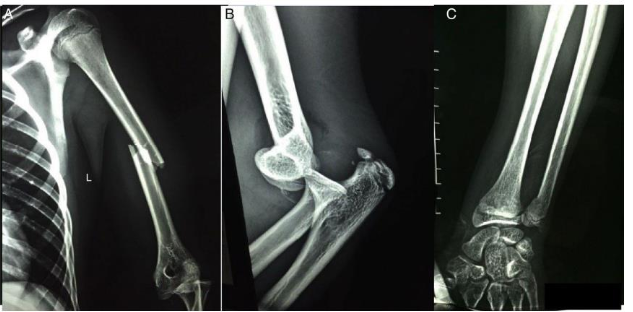

A fratura/ luxação do ombro e do cotovelo necessita da intervenção do ortopedista, sempre o mais breve possível, com redução da fratura (aberta ou fechada), seguida da avaliação da estabilidade articular e do desvio das fraturas. Nos casos crônicos, por falta de condições cirúrgicas ou por negligência, a abordagem cirúrgica, na maioria das vezes, torna-se necessária para redução, estabilização articular e/ou substituição protética. Vários são os exames que podemos realizar de acordo com as condições do paciente.

Com base nessas informações, é correto afirmar: